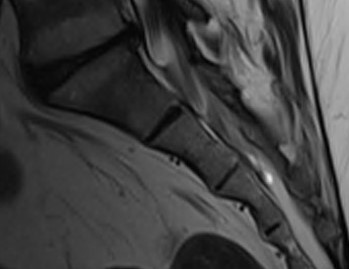

MRI

Show inflammation